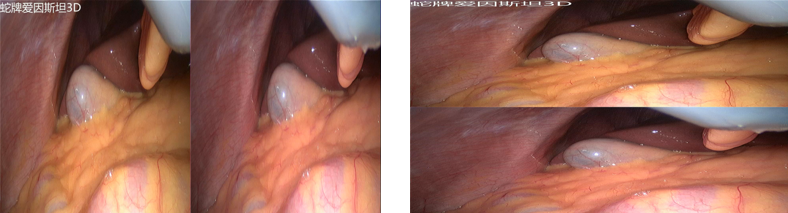

数字化整合—3D信号处理

可接入各种3D信号:双链路SDI、双链路DVI、单路DVI(L&L)可对各种3D信号进行处理:双路拼接成左右、上下画面

L&L信号拆分后拼接成左右、上下画面

可录制各种3D格式:左右、上下、MVC格式(两帧1920*1080图像)

触控屏控制可直接回放3D视频至腔镜主机所配的3D显示器,3D/2D显示模式直接切换,无需调整显示器。还可调整左右眼的顺序。

可将接入的3D信号拼接成左右、上下画面扩展输出到大屏3D电视机,使3D电视机上能实时显示3D腔镜视频